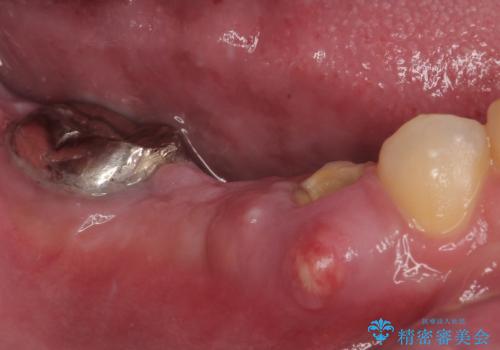

ブリッジの支台歯が痛みを覚え、近医でブリッジを切断してもらって以降、そのままにしてしまったとのことでした。

問題が起きていた手前の歯から膿が出てきたことを自覚して当院を来院されましたが、既に歯根破折をしており、抜歯が必要な状態でした。

咬合力が非常に強い患者様であり、2歯欠損のブリッジ(しかも大臼歯は失活歯)は歯根破折のリスクが高すぎると判断し、抜歯部および欠損部に対して、インプラントによる補綴治療を行うこととしました。